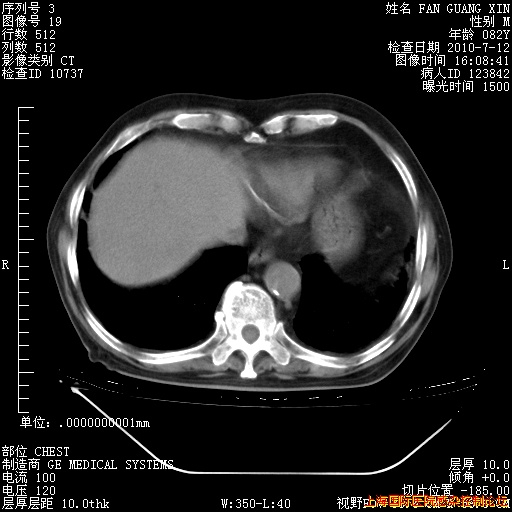

今天复查CT

回复

整整相隔30天的肺部CT好像有所好转啊。甲强龙减量第3天,需要观察体温。